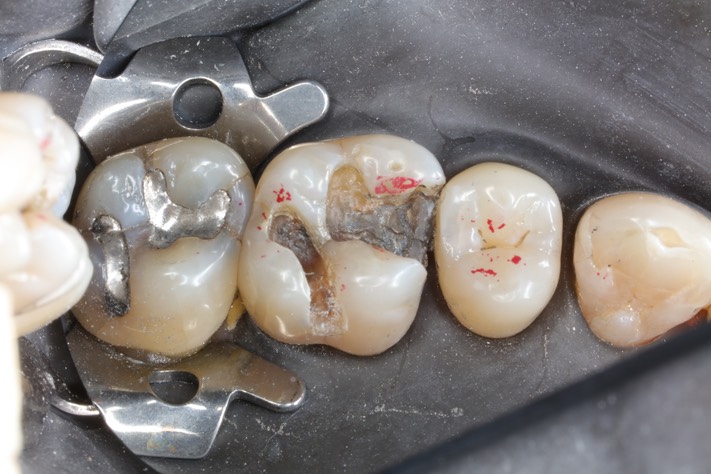

Kyle Chock #14 caries removal